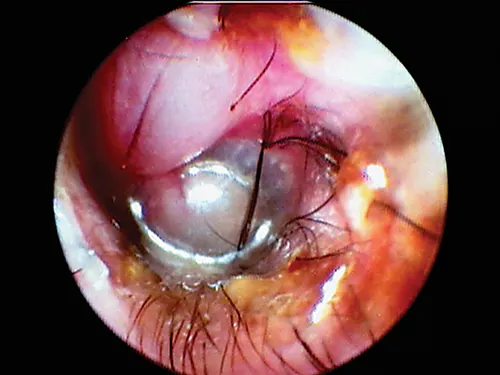

Ceruminoliths, concretions of dried medications, and foreign bodies are more often seen in the horizontal canal. Occasionally, epilated hairs will fall into the horizontal canal and become embedded in the thick wax accumulation along the floor of the horizontal canal. These hairs can be seen occluding the view of the eardrum (Figure 11).

selected slide image

FIGURE 11

1 / 2

Hairs in the horizontal ear canal obstructing the view of the eardrum